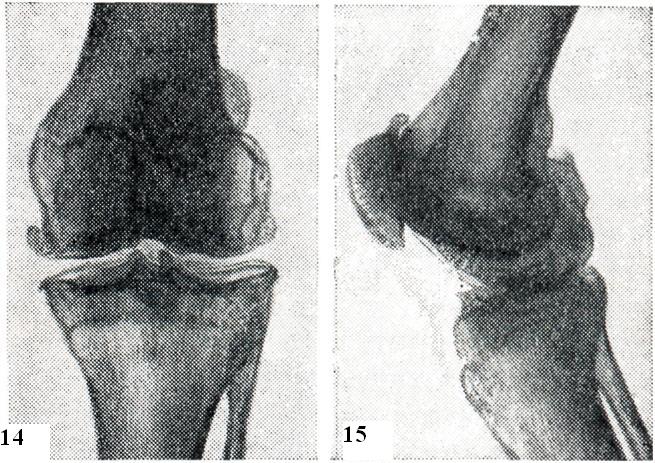

Артроз коленных суставов (гонартроз) встречается так же часто, как коксартроз, но обычно протекает бессимптомно. Поражение этих суставов связано со следующими обстоятельствами: во-первых, коленный сустав имеет большое количество хрящевых образований (кроме большой площади суставного хряща, имеются внутрисуставные мениски, которые выравнивают недостаточно конгруэнтные суставные поверхности костей и служат своеобразными амортизаторами); во-вторых, коленные суставы находятся под постоянной нагрузкой веса тела, особенно у тучных людей; в-третьих, коленные суставы очень часто травмируются.

Последнее обстоятельство обусловливает частое возникновение так назвыаемого хондромаляции надколенника у лиц молодого и среднего возраста, после чего развивается гонартроз. Большую роль в развитии гонартроза играет ожирение: во-первых, существенно увеличивается нагрузка на коленнные суставы; во-вторых, увеличение внутрисуставного отложения жировой ткани затрудняет и без того сложные условия питания суставного хряща. Клинические симптомы гонартроза весьма разнообразны. В начальном периоде отмечаются боли при восхождении, еще больше — при спуске по лестнице, при вставании после покоя, а также в сырую и холодную погоду и после длительного нахождения на ногах. Иногда боли острые, что может быть обусловлено раздражением синовиальной оболочки кусочками оторвавшегося хряща и развитием реактивного синовита. При этом возможно скопление большого количества экссудата и выбухание супрапателлярной сумки и карманов суставной капсулы. Грубый хруст в начальном периоде болезни определяется при пальпации, а в далеко зашедших случаях выслушивается на расстоянии. Отмечается болезненность ниже надколенника, по его краям и при смещении надколенника в медиальном и латеральном направлении. При исследовании синовиальной жидкости обнаруживают умеренное увеличение концентрации белка и увеличение вязкости (в отличие от ревматоидного артрита, при котором вязкость снижена). Число лейкоцитов в ней не превышает 3000 в 1мм3, среди них лишь четверть составляют полинуклеары (при ревматоидном артрите цитоз до 20 000 лейкоцитов в 1 мм3, ¾ из них составляют полинуклеары). Немаловажное значение в дифференциальной диагностике гонартроза с ревматоидным артритом коленных суставов имеет морфологическое исследование материала синовии, полученного при биопсии. На рентгенограммах коленных суставов (рис. 14 и 15) характерные для артроза изменения: сужение суставной щели, подхрящевой склероз, краевые остеофиты и кистовидная перестройка прилегающих частей костей. К числу ранних рентгенологических признаков гонартроза относятся заострения межмыщелковых бугорков болынеберцовой кости. Наблюдаются также мелкие эрозии в нижней трети задней поверхности надколенника, сужение щели между надколенником и бедренной костью и остеофиты на верхнем и нижнем краях надколенника. При гонартрозе часто поражаются суставные мениски, особенно медиальный. Это приводит к резкому сужению суставной щели или к О-образной или Х-образной деформациям. Гонартроз может быть вторичным (в результате травм, перенесенных артритов, повреждений менисков, расслаивающегося остеохондрита, хондроматоза и другого) либо первичным (возникающим без заметной причины, возможно, в результате старения хряща или длительной профессиональной перегрузки). Чаще, чем артроз другой локализации, гонартроз осложняется синовитом. В этом случае говорят о гонартрозе с реактивным синовитом.